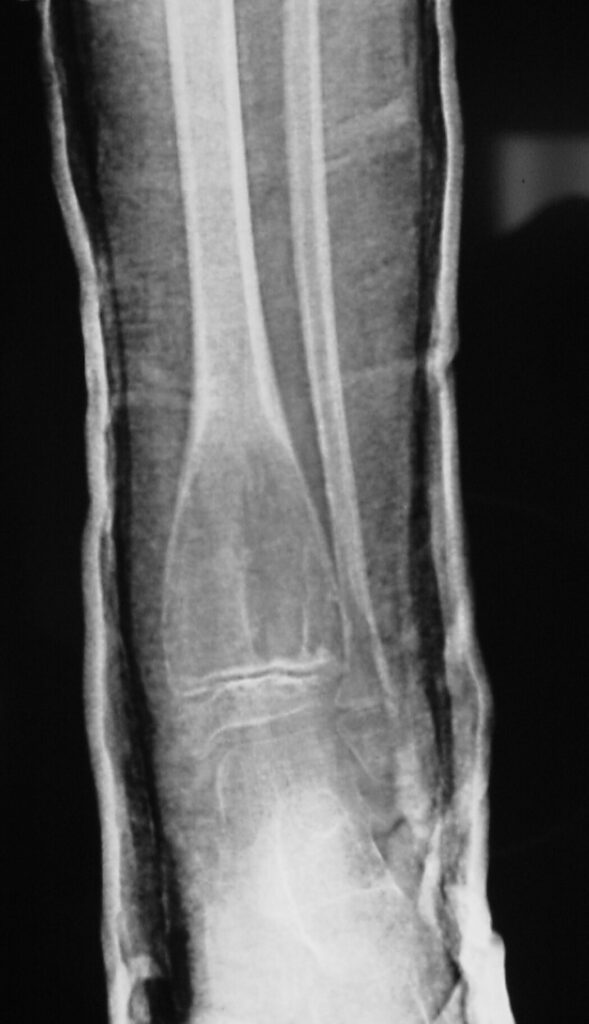

Fig 1a. Plain X-ray (AP View). ABC of the Distal Tibia: Geographic Well Circumscribed Lesion in the distal tibia. The cortices are expanded. There are internal septations. There is no internal mineralization. There is no evidence of a malignant appearing periosteal reaction such as a sunburst or hair on end pattern or codman’s triangle.

Plain x-ray

• Radiolucent

• Geographic and Eccentric lesion that is well circumscribed

• May scallop or expand the surrounding cortex

• Surrounded by sclerotic bone

• Methaphyseal region most common

• Eccentric

• Elevation of the periosteum could be seen as a benign appearing periosteal reaction (continuous periosteal reaction)